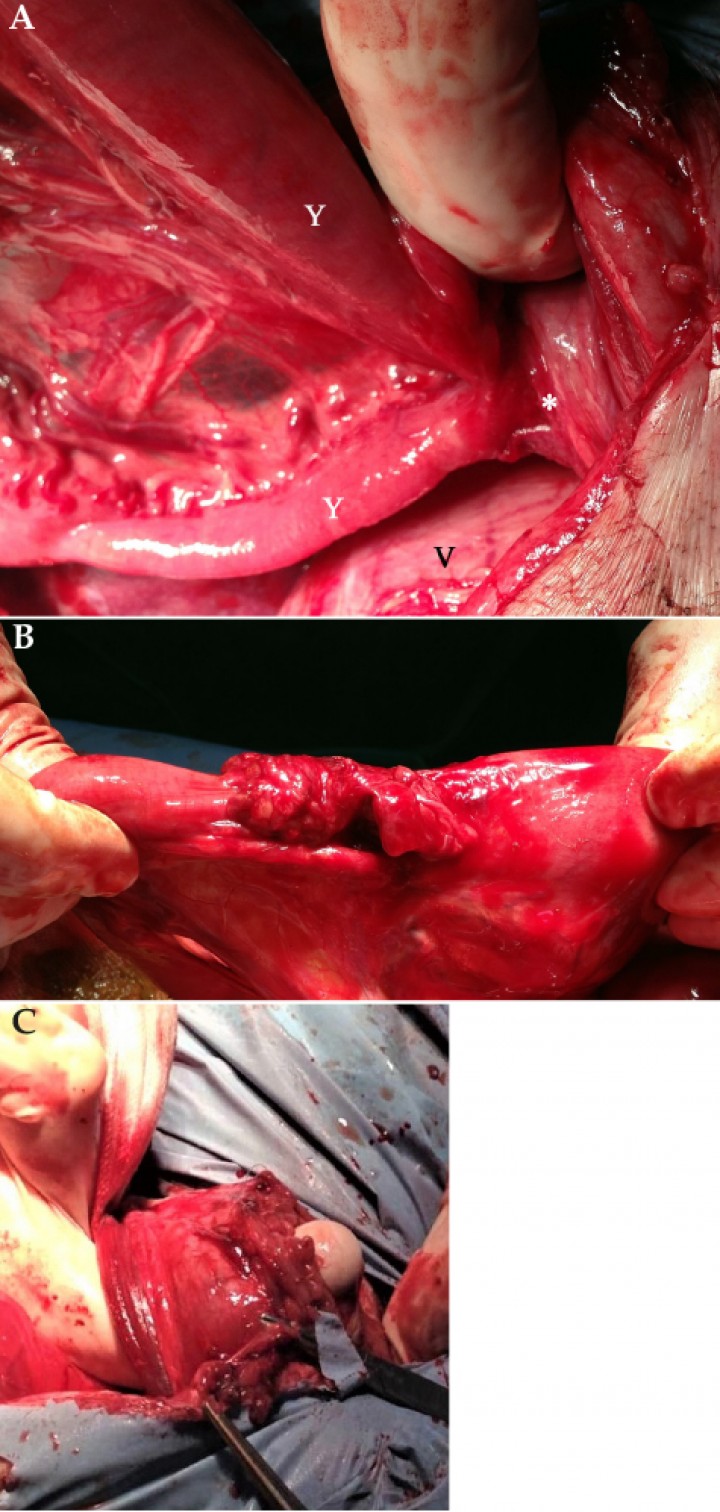

Durante la cirugía se observó presencia de líquido libre en cavidad abdominal de color verdoso. En la zona de la piel donde se localizaban las fístulas al lado del prepucio, por su cara interna en la pared abdominal, se evidenciaba un pequeño defecto de menos de 1 cm, en el que se hallaba incarcerado un fragmento de yeyuno (Figs. 5A y B), que se encontraba perforado, viéndose la fuga de contenido intestinal hacia la cavidad abdominal. Se hizo la disección roma de la zona intestinal incarcerada y posteriormente, debido a su aspecto congestivo y a la presencia de perforación en su pared, se practicó una enterectomía y omentalización. No fue necesario cerrar el defecto de la pared abdominal, ya que quedó estanco tras retirar el segmento incarcerado. Para finalizar la cirugía, se realizó el lavado de la cavidad abdominal con abundante cantidad de suero salino fisiológico atemperado, colocándose un drenaje activo (Jackson Pratt®, Everest tecnología veterinaria. Barcelona.

<p>Imágenes de la intervención quirúrgica. (<strong>A</strong>) Detalle del asa intestinal incarcerada (Y) en la que se observa cómo se introduce hacia un defecto en la pared abdominal (asterisco), adyacente a la vejiga de la orina (V). (<strong>B</strong>) Asa intestinal incarcerada, una vez liberada de su incarceración en la pared abdominal. (<strong>C</strong>) Defecto de la pared abdominal, en el lateral derecho del prepucio, donde se encontraba incarcerada el asa intestinal.</p>

Imágenes de la intervención quirúrgica. (A) Detalle del asa intestinal incarcerada (Y) en la que se observa cómo se introduce hacia un defecto en la pared abdominal (asterisco), adyacente a la vejiga de la orina (V). (B) Asa intestinal incarcerada, una vez liberada de su incarceración en la pared abdominal. (C) Defecto de la pared abdominal, en el lateral derecho del prepucio, donde se encontraba incarcerada el asa intestinal.